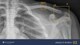

Dette bruddet ble ikke påvist av en lege.

Men av kunstig intelligens.

Hvis du i dag havner på Bærum sykehus fordi du tror du har brukket noe og må ta røntgen, vil kunstig intelligens (KI) analysere røntgenbildet.

Det er altså et dataprogram som vil være med på å avgjøre om du har brudd, eller om du kan sendes hjem.

Programmet har trent seg opp ved å analysere hundretusener av beinbrudd verden over. Nå leter algoritmen etter brudd hos norske pasienter.

Den algoritmen som nå settes i arbeid på Bærum sykehus, heter Boneview og finner beinbrudd på røntgenbilder.

Radiograf Jonas Vatle peker på røntgenbildet på PC-skjermen. Tåen på bildet tilhører en av de første pasientene i landet som blir analysert ved hjelp av kunstig intelligens.

– Her ser vi en oransje boks som viser bruddet hos pasienten. Det som skjer nå, er at pasienten blir sendt til ortopedisk mottak for videre behandling for bruddet, sier han.

Algoritmen har brukt to minutter på analysen, noe som skal bety mindre ventetid på pasientene.